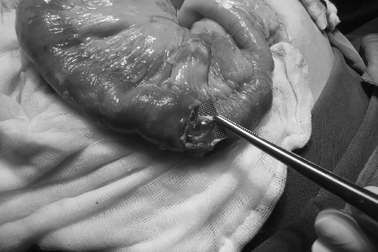

Uống thuốc còn nguyên vỉ cụ bà bị thủng ruột, phân tràn ổ bụngNhập viện trong tình trạng đau bụng, nôn ói, sốc nhiễm trùng cụ bà 79 tuổi được bác sĩ xác định có dị vật gây thủng ruột. Các bác sĩ thực hiện cuộc mổ hở lấy ra viên thuốc còn nguyên vỉ đã cắt thủng 2 lỗ ở ruột non khiến phân tràn ra ổ bụng.